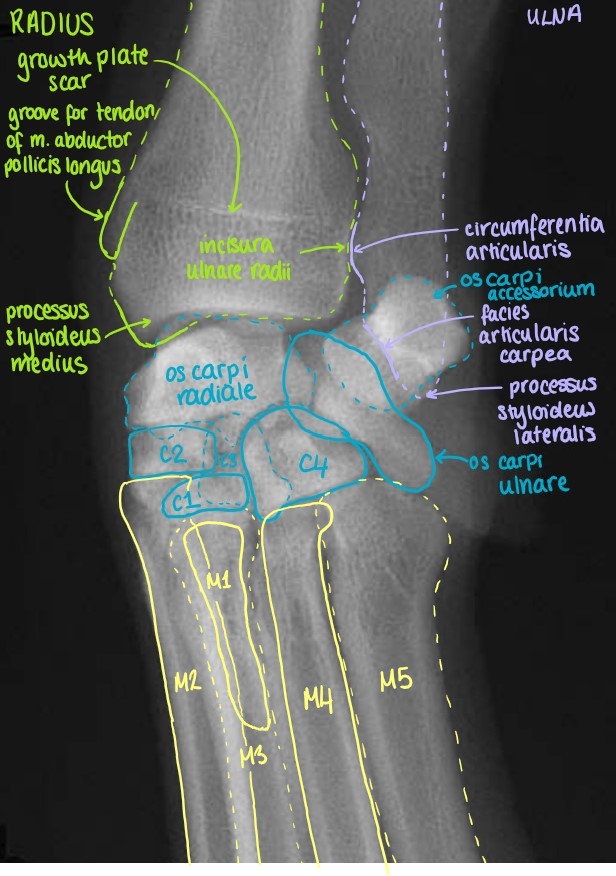

Articulatio Carpi